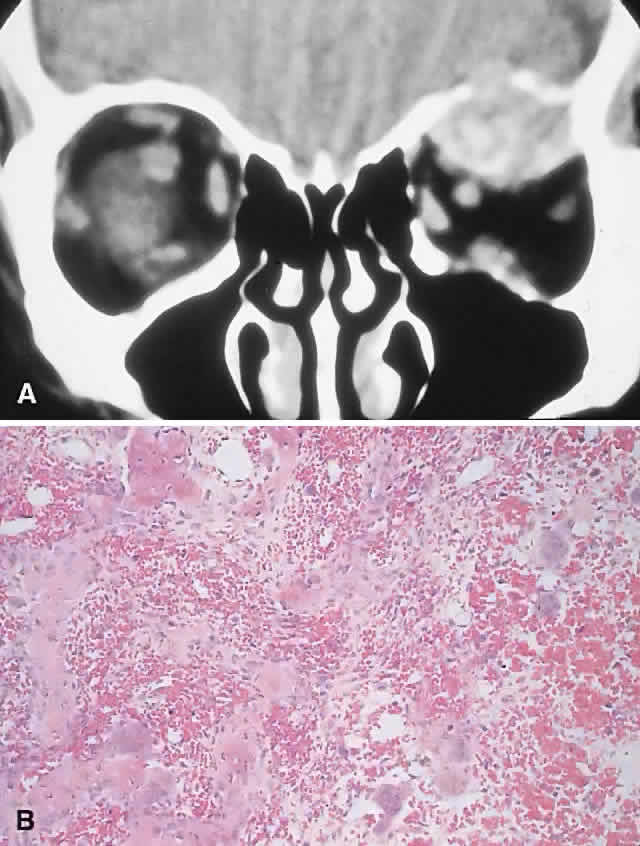

| The above clinical patterns correlate reasonably well with the following